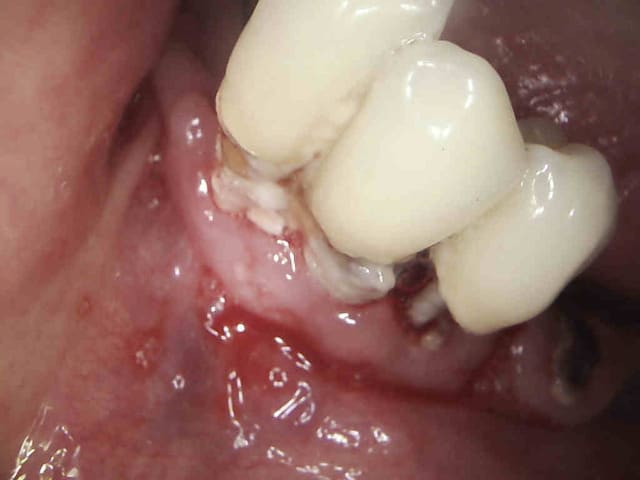

C'est quoi la proba d'avoir une deuxième bio à 5 canaux en 2 semaines?

(la radio excentrée est dégueulasse, mais ça montre les doubles courbures, quelques peu minimisées par l'angulateur...